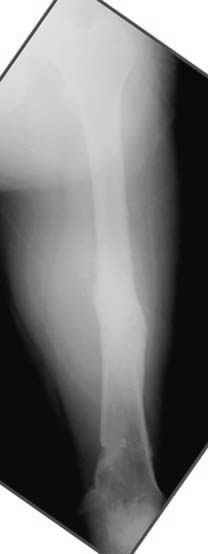

Несколько снимков из моей коллекции, чтобы разьяснить, почему мы до сих пор делаем различные варианты остеотомии.

На рисунке N1 предоперационный план лечения ложного сустава шейки бедра- линия ложного сустава, угол и направление введения импланта, клиновидная остеотомия в градусах и миллиметрах, второй снимок после коррекции, расчет, на сколько удлиняется конечность и размеры импланта;

N3 рисунок окончательный снимок, после операции моя рентгенограмма должен выглядеть примерно как эта картина. На N4 снимке клин перед удалением; N5 послеоперации 3 нед.; N6 окончательная рентгенограмма.

(доложен в Ст. Петербурге 2003 и в Москве 2004)

варус при проксимальном отделе 95 градусной пластиной.